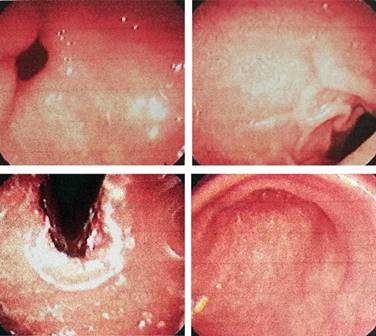

Paciente femenino de 66 años, no cuenta con antecedentes personales de importancia; manifiesta dolor en epigastrio, tipo urente, con irradiación retroesternal, refiere regurgitaciones y pirosis, sintomatología que mejora con el uso de inhibidor de bomba de protones y sucralfato, tratamiento que ha llevado de manera crónica, con eventos de remisiones y exacerbaciones, por lo que se inicia protocolo de estudio en sospecha de reflujo gastroesofágico. Se solicita endoscopia, la cual reporta probable dismotilidad esofágica tipo A de acalasia y gastritis leve antral (Figura 1). Con este resultado se solicita estudio contrastado y manometría.